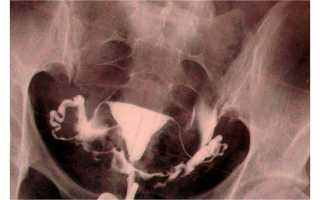

Чтобы с высокой точностью диагностировать спайки в малом тазу, женщине потребуется пройти сальпингографию или соносальпингографию. Сальпингография представляет собой рентгенографическое исследование. Маточные трубы пациентки заполняют специальным раствором, после чего выполняют несколько рентгенологических снимков. Благодаря раствору на них будут четко видны образования в придатках матки, если они там имеются. Сальпингографию проводят перед овуляцией. Это рекомендуется сделать для того, чтобы рентгенологические лучи не нанесли вреда здоровью плода, если вдруг произошло зачатие.